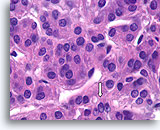

Afbeelding 13

Benigne, hyperplastisch/adenomatoïde nodule, schildklier FNA, celblok.

Het celblok dat overeenkomt met afbeelding 11-12 toont een duidelijk bijvoeging van micro- en macrofollikels. Er zijn twee kenmerken die voor een benigne nodule pleiten. Het eerste is dat de microfollikels afgeplat cytoplasma vertonen, vergeleken met de robuuster uitziende macrofolliculaire cellen (vergelijk de hoogte van het cytoplasma bij de twee pijlen). Een tweede kenmerk is de variatie in het uiterlijk van het colloïd tussen de verschillende follikels. Let op het oedemateuze colloïd in het ene follikel dat zich naast een follikel bevindt met dicht opeengepakt colloïd (open pijlen). Van benigne hyperplastisch/adenomatoïde nodulen wordt verwacht dat ze heterogeniteit vertonen, terwijl folliculaire neoplasmen monotoner zijn.

40X

Afbeelding 13

Benigne, hyperplastisch/adenomatoïde nodule, schildklier FNA, celblok.

Het celblok dat overeenkomt met afbeelding 11-12 toont een duidelijk bijvoeging van micro- en macrofollikels. Er zijn twee kenmerken die voor een benigne nodule pleiten. Het eerste is dat de microfollikels afgeplat cytoplasma vertonen, vergeleken met de robuuster uitziende macrofolliculaire cellen (vergelijk de hoogte van het cytoplasma bij de twee pijlen). Een tweede kenmerk is de variatie in het uiterlijk van het colloïd tussen de verschillende follikels. Let op het oedemateuze colloïd in het ene follikel dat zich naast een follikel bevindt met dicht opeengepakt colloïd (open pijlen). Van benigne hyperplastisch/adenomatoïde nodulen wordt verwacht dat ze heterogeniteit vertonen, terwijl folliculaire neoplasmen monotoner zijn.

40X